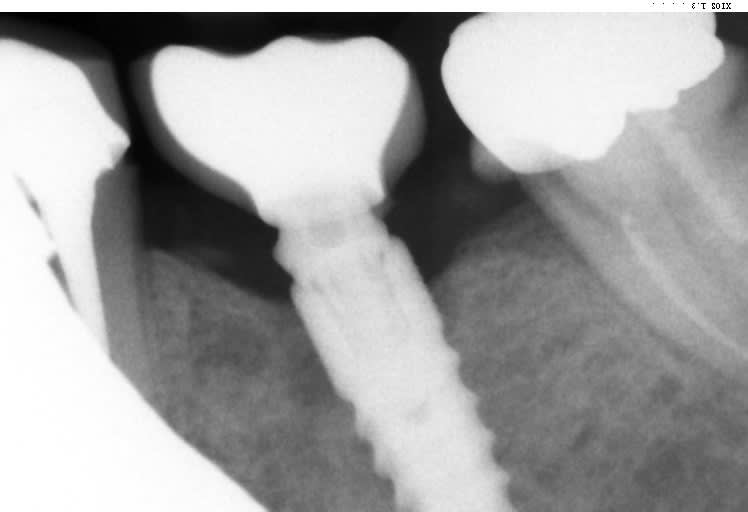

Bonjour, je ne parviens pas à identifier cet implant.

Implant posé par un confrère de St Omer il y a qq années et qui a mis fin à ses jours depuis.

TIOLOGIC DENTAURUM